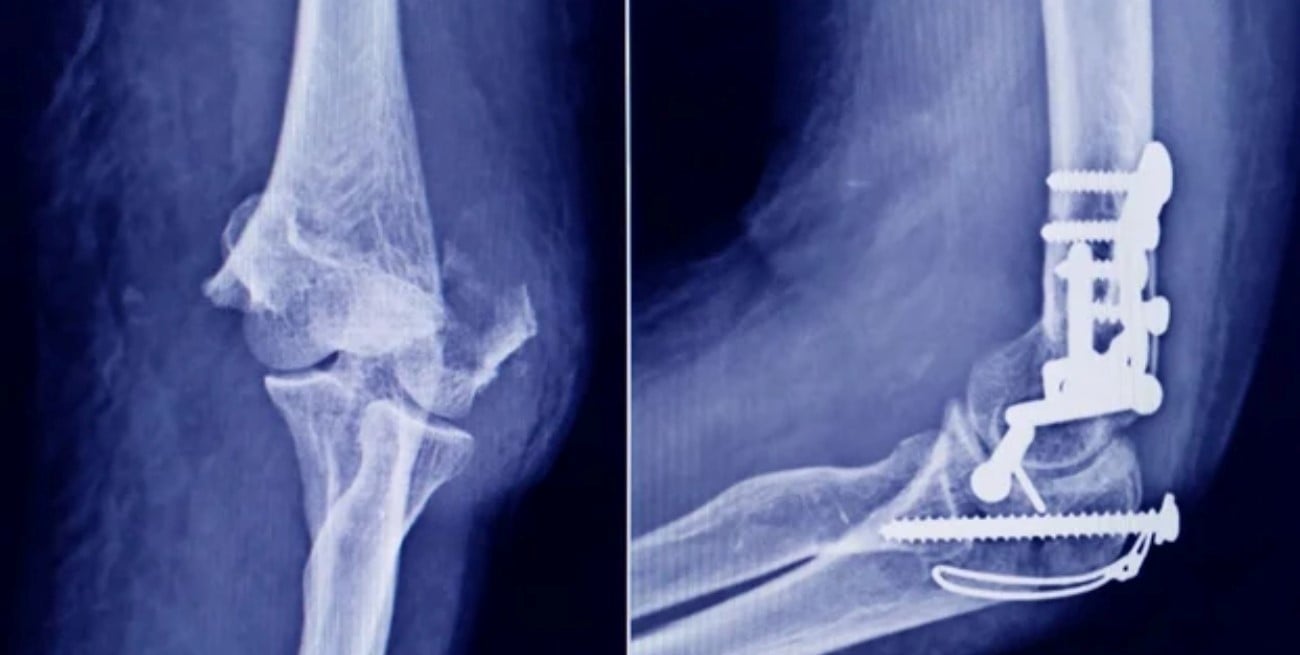

El tornillo en cuestión corresponde a un insumo habitualmente empleado en intervenciones traumatológicas y figura como fabricado por la empresa Stryker Corporation, registrada ante la ANMAT bajo el número PM 594-139.

Según precisaron desde el organismo, el tornillo identificado presenta las siguientes características: STRYKER 10 mm x 28 mm – BIOABSORBABLE – ACL INTERFERENCE SCREW – REF 234-010-067 – LOT 90905.

La ANMAT detalló una serie de inconsistencias que permitieron confirmar la falsificación del producto. Entre las principales diferencias detectadas se encuentran:

- El tornillo original cuenta con fecha de vencimiento, mientras que el producto falsificado no incluye este dato.

- La empresa Stryker nunca utilizó envases tipo pouch de la marca 3M para este insumo.

- El producto auténtico se esteriliza mediante radiación gamma, mientras que el falso habría sido esterilizado por vapor o formaldehído.

- El tornillo original es de color gris opaco, mientras que el falsificado es incoloro y puede observarse a través del envase transparente.

Estas irregularidades refuerzan la advertencia sobre la falta de garantías en cuanto a origen, composición, seguridad y aptitud del producto.

Desde la ANMAT subrayaron que, al tratarse de un producto falsificado, su uso representa un riesgo directo para la salud del paciente al que se le implante. Por ese motivo, recomendaron no utilizar el tornillo identificado y comunicarse de inmediato con el organismo en caso de tenerlo en poder.